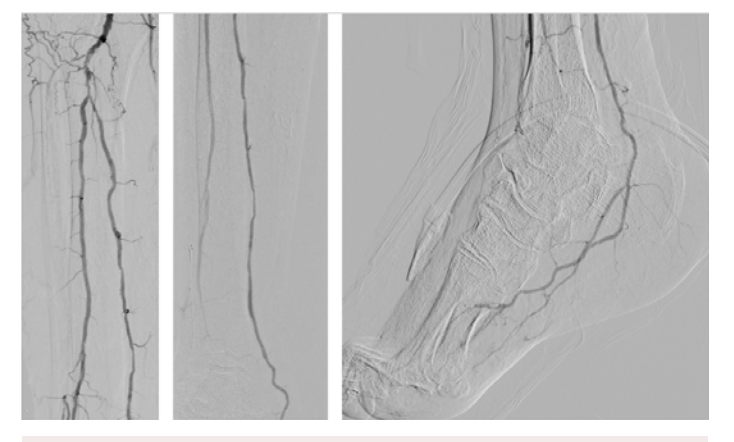

The patient had a right transradial aortogram with selective right leg angiogram. His angiogram revealed adequate inflow with patent aorto-iliac, common femoral, superficial femoral, profunda, and popliteal vessels. Distally he had a chronically occluded (CTO) right anterior tibial (AT) with a hibernating dorsalis pedis artery (DP) that faintly filled from a peroneal (PER) collateral, 90% tibial peroneal trunk (TPT) stenosis, multiple 75% lesions in the proximal and mid posterior tibial artery (PT), and a patent lateral plantar artery (LP) (Figure 1).